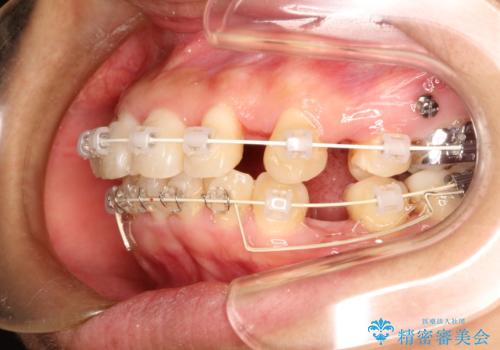

- 矯正装置

- 審美装置

- 治療期間

- 2年2ヶ月

がたつきの度合いが強いのと、口元をなるべく引っ込めたい希望がありましたので、ワイヤーでの抜歯矯正となりました。

ガタガタが重度の方は抜歯が必要となることが多いです。

抜歯スペースを使って前歯を引っ込めることにより、口元の突出感も改善できました。